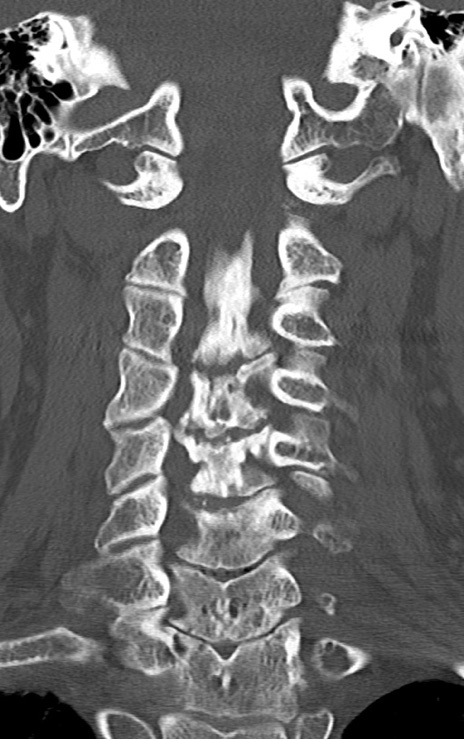

頚椎CT

矢状断像